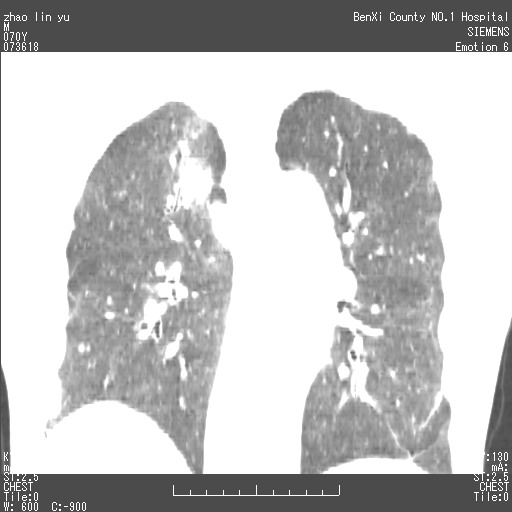

以下是引用王靖旗在2007-7-10 17:12:00的发言:[br] 男、70、咳嗽两个月,半年前换瓣手术,胸片未见异常,于昨天行x片发现右肺上野大片影,行ct扫描,这里是减薄图像,余肺正常。明天晚上会有增强扫描片,到时我会上传。[br][br] 冠状位请大家细看,应该是有意义的,[br][br] 请大家先看平扫发表意见。[br][br]

[br]冠状面[br]